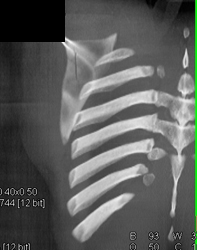

Scapular Fracture